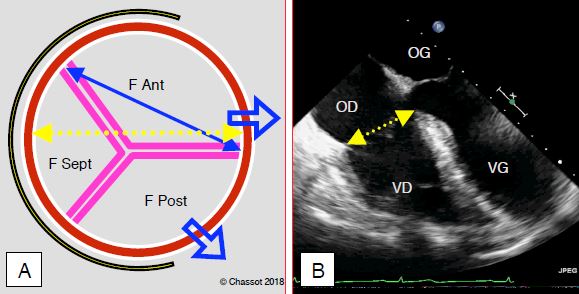

Figure 11.151 : Valve tricuspide et mesures du diamètre de l’anneau tricuspidien. A : schéma de la valve vue depuis l’OD ; le septum est sur la gauche de l’image. La valve est de forme elliptique. Les trois feuillets de la valve tricuspide sont de tailles inégales : le feuillet antérieur est le plus grand, le feuillet postérieur est de taille moyenne, et le feuillet septal est plus petit et plus restrictif. L’anneau fibreux tricuspidien (en jaune) est incomplet ; il ne s’étend pas à la partie postéro-latérale. Lors de dilatation, la valve s’agrandit dans la direction postéro-latérale (flèches bleues), là où l'anneau fibreux est interrompu. B: vue échocardiographique transoesophagienne en 4-cavités; le diamètre normal est de 2.8 ± 0.5 cm ; la dilatation est significative lorsqu’il est ≥ 4.0 cm [1]; ces images bidimensionnelles sous-estiment le diamètre anatomique réel. Dans le champ opératoire, le diamètre est mesuré entre la commissure antéro-septale et la commissure antéro-postérieure (double flèche bleue en A). En B, on voit bien le décalage d’environ 1 cm qui existe entre l’insertion septale de la valve tricuspide et celle de la valve mitrale; il correspond à la partie fibreuse du septum interventriculaire.

Mesuré en vue échocardiographique 4 cavités, le diamètre normal est de 2.8 ± 0.5 cm (2.5-3.9 cm) en diastole; la dilatation est significative lorsqu’il est ≥ 4.0 cm (2.1 cm/m2) (Figure 11.151) [1,3,4]. La dilatation de l’anneau tricuspidien et de la paroi libre du VD entraîne une insuffisance tricuspidienne (IT) parce que les feuillets antérieur et postérieur ne peuvent plus se rejoindre en systole (Vidéo et Figure 11.152).